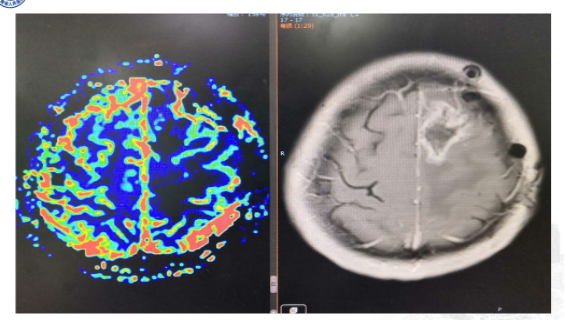

复查MRI提示:局部病灶强化,PWI提示局部灌注有缺失,考虑病情进展,同时不除外假性进展,患者脑水肿范围较大。

根据以往经验调整治疗方案:1、根据复发胶质瘤相关指南,首选抗血管生成药治疗;2、MDT讨论:病灶累积胼胝体,再次手术难度大;3、给予“阿帕替尼425mg qd po”。之后显示水肿变小,灌注降低。继续原方案治疗。

8月份复查再次显示肿瘤进展,由于没有更好的治疗方案,所以暂时继续原方案治疗。